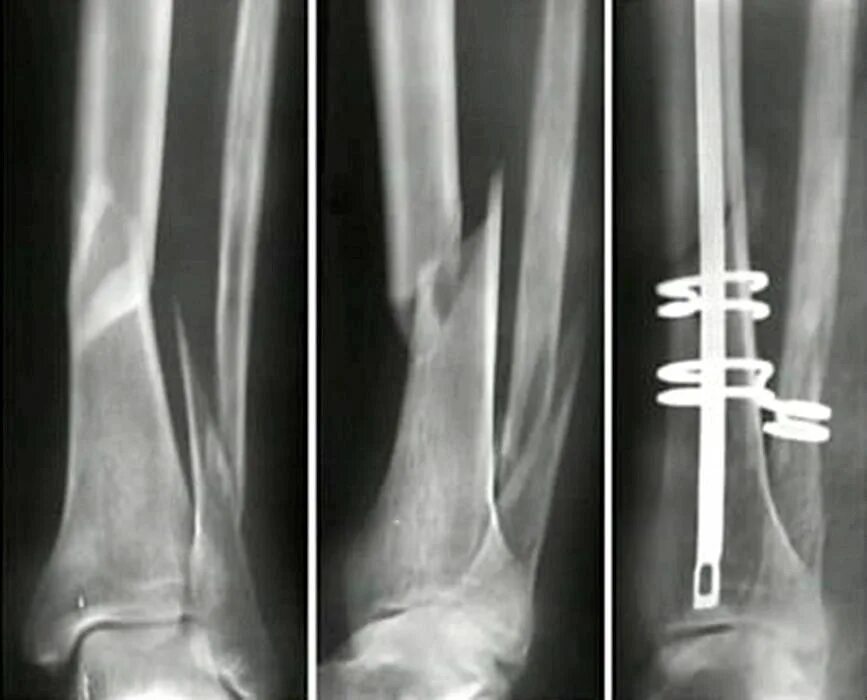

Сколько срастается малая берцовая